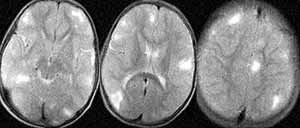

Больной У. 4 года. При поступлении жалобы на судорожные приступы, умственную отсталость, глубокую задержку психоречевого развития. Судороги кивательные, 1-2 серии в день. Ребенок ходит; СПР D<S, высокие. На теле выявлены депигментированные пятна размером до 12 мм. При проведении краниальной МРТ определяются очаги гиперинтенсивные в Т2W и изогипоинтенсивные в Т1W, расположенные преимущественно кортикально и субкортикально. Субэпендимальные очаги явно не визуализируются, возможно, вследствие кальцинации (Рис. 2). (Собственное наблюдение, исследование проведено на базе республиканской клинической психиатрической больницы; МР-томограф «Образ-2М» 0.14 Тл.).

[Увеличить]

Рис. 2. МР-томограммы головного мозга, Т2-взвешенные изображения. Выявляются множественные очаги гиперинтенсивные в Т2W.